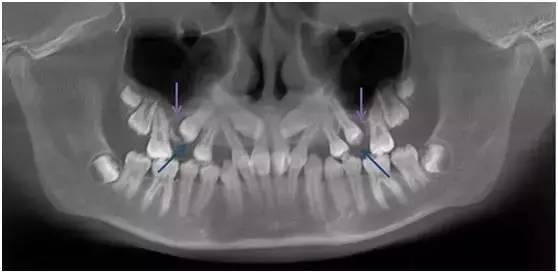

局部解剖异常

局部解剖异常造成牙齿萌出受限在临床上比较少见,但治疗难度比较大,而且往往需要多学科配合。

下面这位患者就是因为上颌窦气化过于充分,窦底接近牙槽基骨的顶端(如图紫色箭头处),造成双尖牙区域牙槽基骨骨量不足,第二双尖牙无法正常萌出(如图蓝色箭头处)。

这种情况即使进行正畸治疗,也会因为局部骨量不足,出现第二双尖牙无法牵引到位或根周骨量不足的风险。

因此患者接受了上颌窦底提升植骨术,一年后牙槽基骨成骨充分,牙齿自行正位萌出。此时再进行正畸治疗,难度和风险将大大减小。